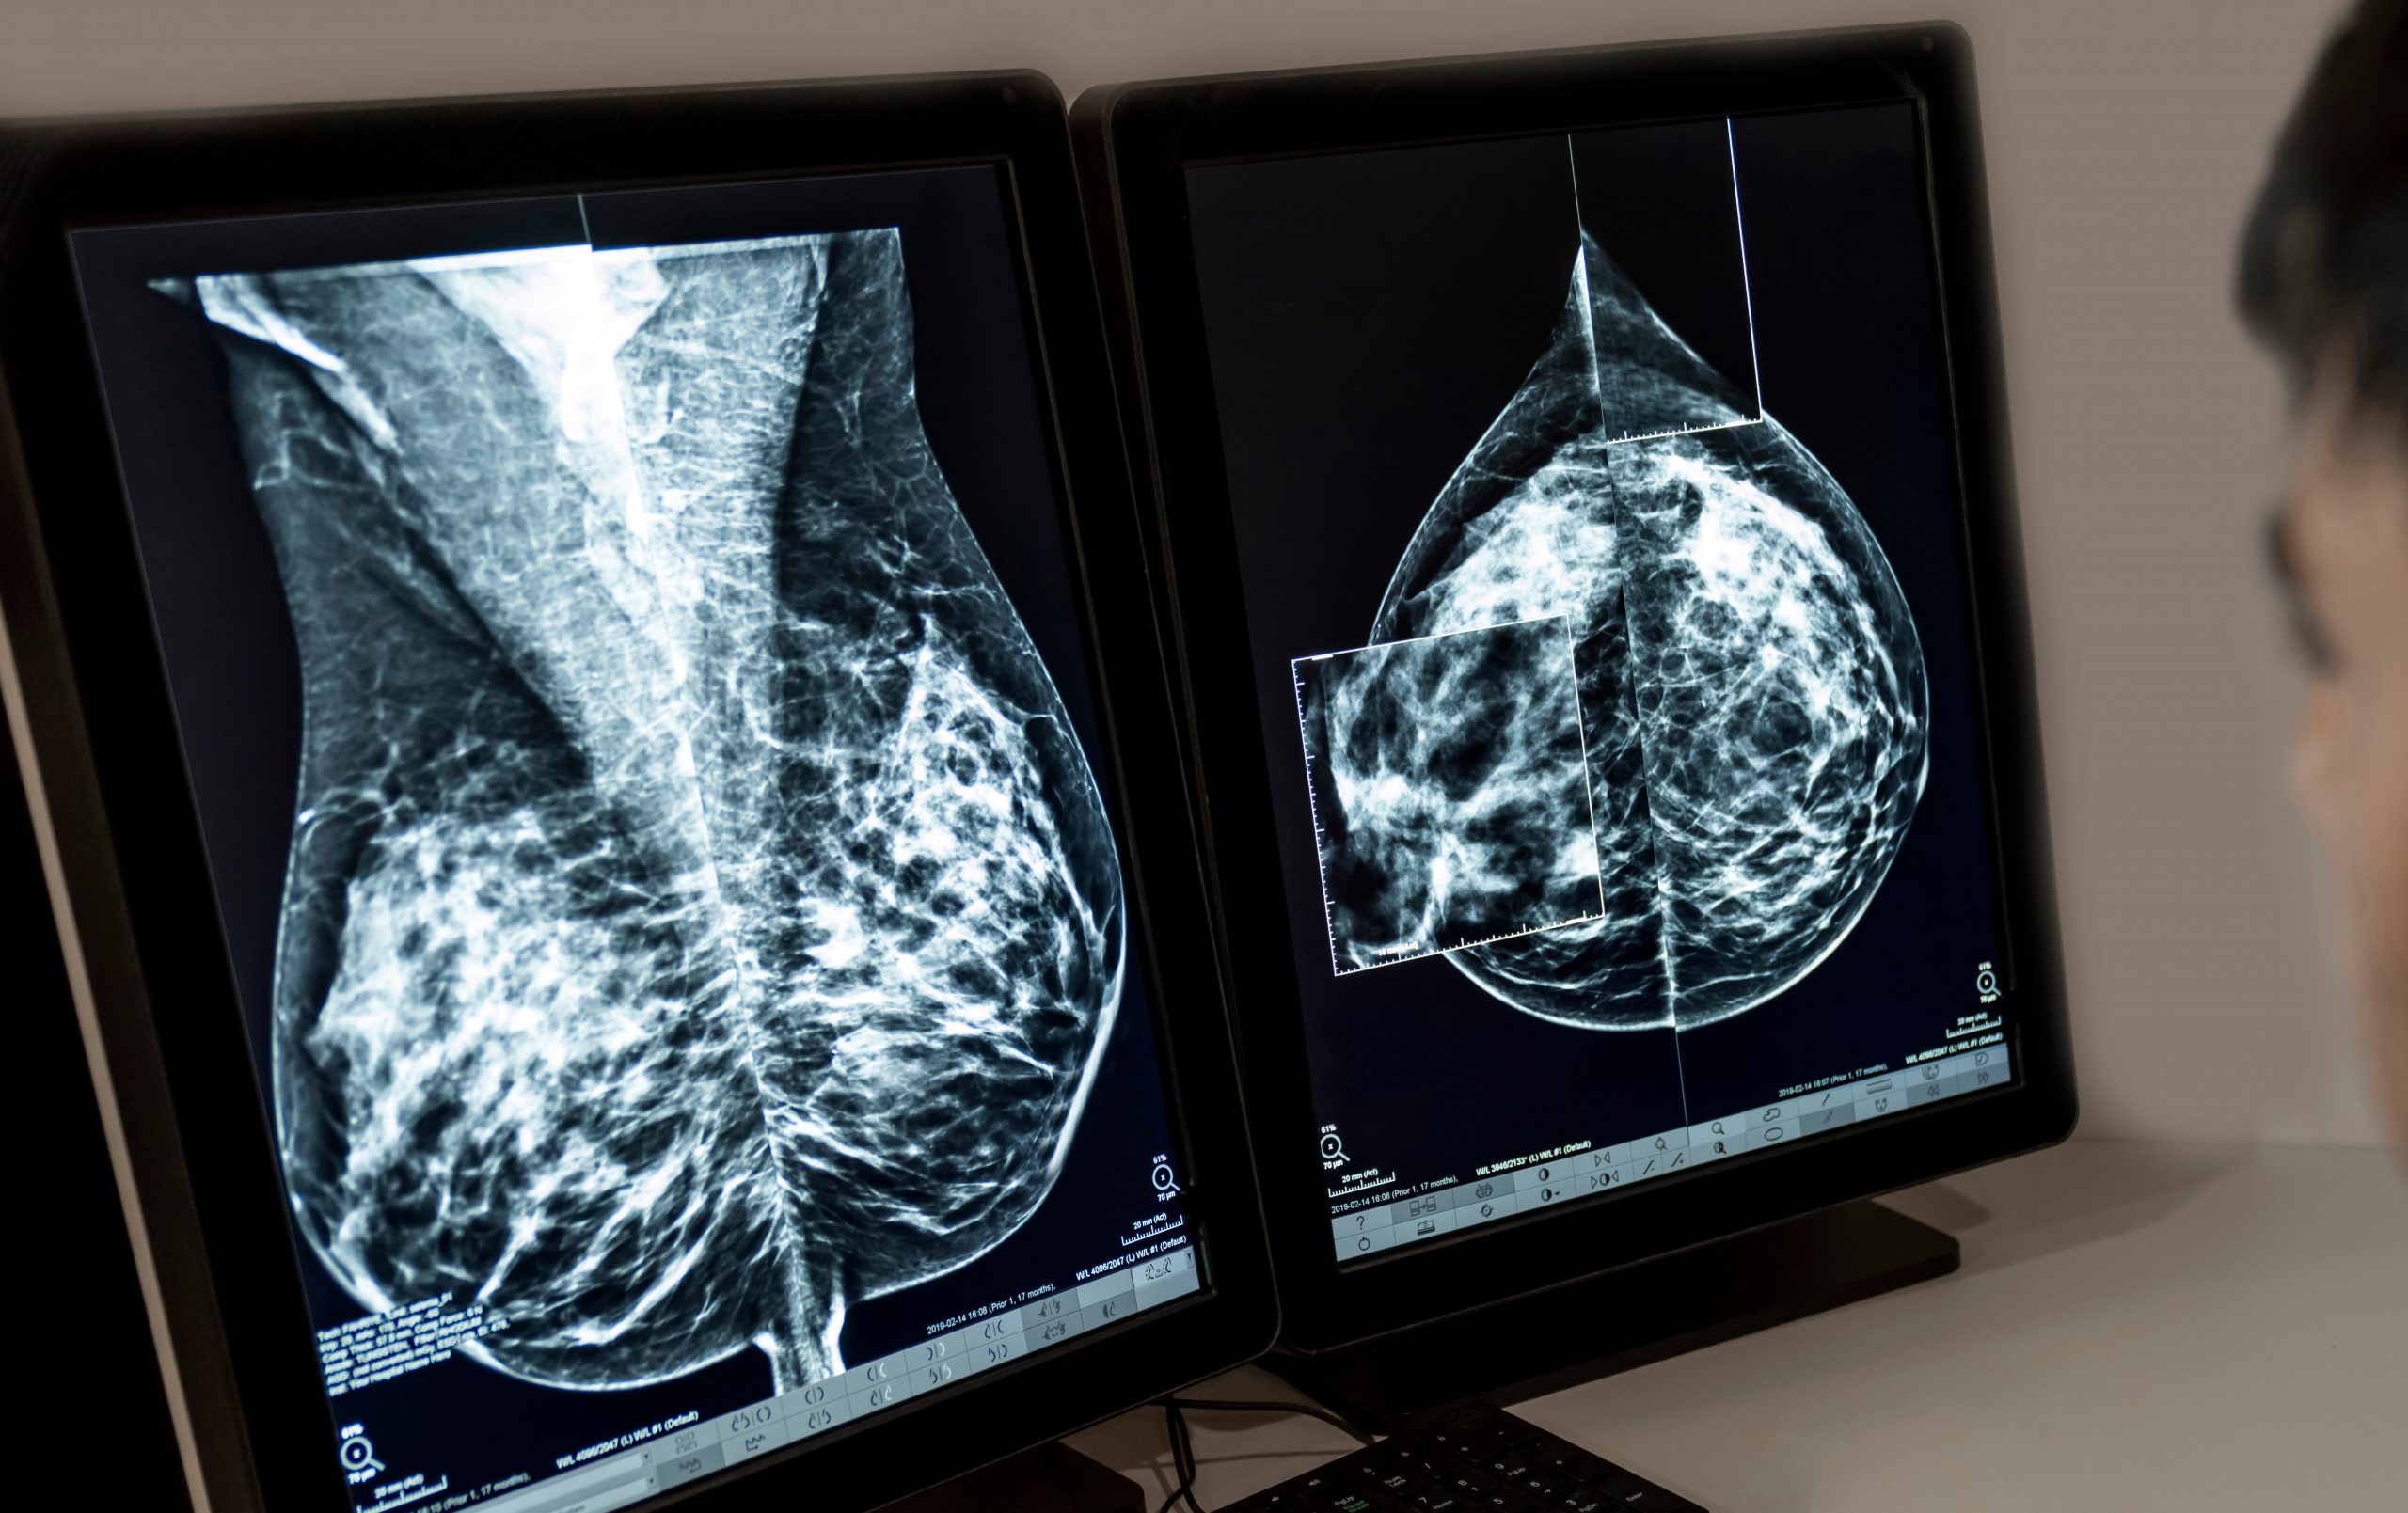

A new US collaboration will see the launch of a mobile mammography unit that aims to address gaps in access to care.

Part of a larger mobile clinic, a converted RV equipped with a mammography unit aims to encourage improved uptake of regular screenings for people who would normally have to travel for their screenings.

The unit has been launched by Blue Plus, the health maintenance organisation (HMO) affiliate of Blue Cross and Blue Shield of Minnesota (Blue Cross), and Odam Medical Group.

“Early detection for breast cancer can vastly improve health outcomes,” said Dr. Robert Larbi-Odam, founder of Odam Medical Group.

“Adding mammograms to our services will make it easier for patients to get their recommended screenings, especially in counties where they would otherwise need to travel long distances for an appointment.”